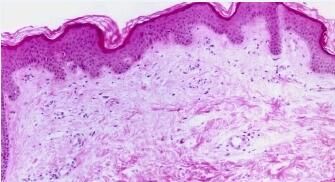

荨麻疹不仅是成人的多发病,也是儿童的常见病症。因其年龄不同,虽然同患荨麻疹,据临床医学专家深入研究发现,两者之间还是很大的区别,小儿荨麻疹的特点是:多是过敏所造成的,其较为常见的病症因首先是食物,其次是病毒感染。那么下面就请北京京城皮肤医院为您具体的介绍一下吧。